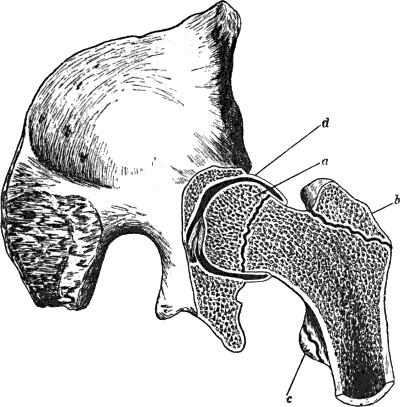

29 12.Os Innominatum showing new Socket formed after Old-standing Dislocation

41 13.Oblique Fracture of Right Clavicle in Middle Third, united